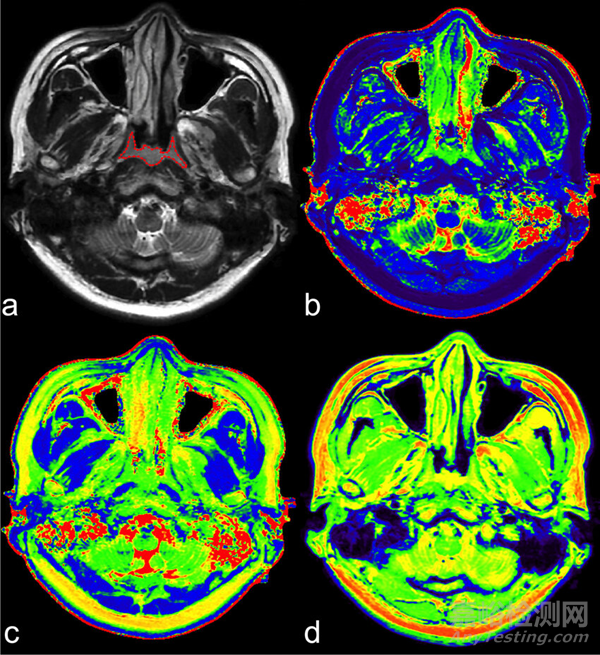

SyMRI 3D 能夠?qū)Υ竽X區(qū)域進(jìn)行精確的體積估計(jì),這種技術(shù)通常稱為 parcellation,它使臨床醫(yī)生能夠更深入地了解大腦結(jié)構(gòu)和功能。此外,SyMRI 3D提供的分辨率有助于全面的病變分析,確保對(duì)醫(yī)療狀況進(jìn)行更準(zhǔn)確和深入的評(píng)估。

SyMRI 3D這一創(chuàng)新解決方案旨在重新定義診斷能力,在SyMRI的后處理領(lǐng)域提供先進(jìn)的應(yīng)用。值得注意的是,SyMRI 3D 提供精確的大腦區(qū)域分析和全面的病變?cè)u(píng)估,具有出色的各向同性分辨率。通過(guò)將 3D 成像引入定量值和組織分割,它有望實(shí)現(xiàn)與 SyMRI 已建立的 2D 成像相當(dāng)?shù)木取yMRI 3D獲得 FDA 批準(zhǔn),這證明了其重塑臨床實(shí)踐的潛力,為醫(yī)療專(zhuān)業(yè)人員提供了無(wú)與倫比的準(zhǔn)確診斷和治療工具。

通過(guò)在SyMRI的后處理解決方案中引入一系列創(chuàng)新應(yīng)用,SyMRI 3D有望徹底改變醫(yī)學(xué)成像。它的主要功能之一在于通過(guò)一種稱為“包裹”的技術(shù)提供大腦區(qū)域的精確體積估計(jì)。這使臨床醫(yī)生能夠更深入地研究大腦的結(jié)構(gòu)和功能,從而更好地了解神經(jīng)系統(tǒng)疾病。

此外,SyMRI 3D 提供的卓越各向同性分辨率有助于全面的病變分析,確保對(duì)各種醫(yī)療狀況進(jìn)行更準(zhǔn)確和徹底的評(píng)估。這種先進(jìn)的成像序列將三維分辨率引入定量值和組織分割,保持了與 SyMRI 的 2D 成像相同的精度水平。